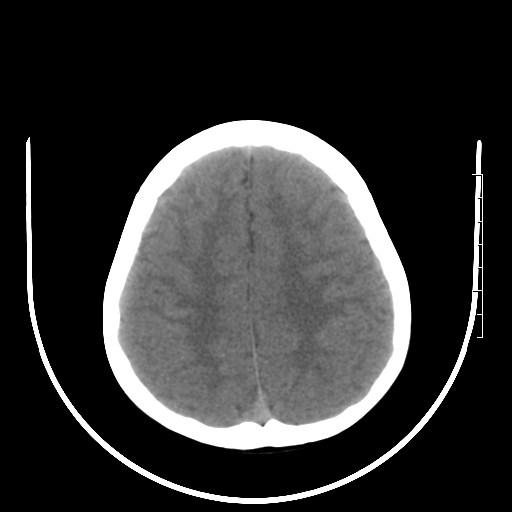

标题: PED3377:m、9y,恶心、呕吐,每月发作2-3次。 [打印本页]

标题: PED3377:m、9y,恶心、呕吐,每月发作2-3次。

正常

颅脑ct轴位平扫颅内未见明确异常。

头颅ct平扫未见异常

颅脑ct平扫未见异常。